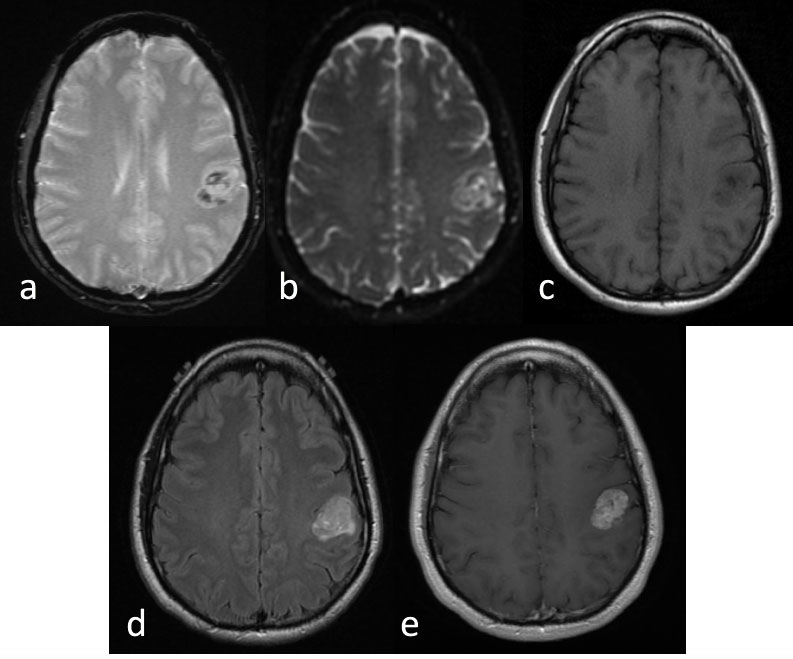

MRI features include a heterogeneous appearance on both T1/T2 weighted imaging related to foci of hemorrhage, necrosis, calcification, and increased vascularity [10]. The tumor may demonstrate high signal on diffusion weighted images (DWI) with associated low signal on apparent diffusion coefficient (ADC) maps due to the increased cellularity of the tumor (Figure 3).

Figure 3: Anaplastic ependymoma.

MRI Brain a) Axial gradient recalled echo; b) Axial ADC map; c) Axial T1 pre contrast; d) Axial T2-Flair; e) Axial T1 post-contrast.

35-year-old left handed man presented with 6 months of progressive right thumb and facial numbness. MRI brain reveals a lobular and avidly enhancing left parietal mass centered in the left post central gyrus, with slight mass effect on the pre central gyrus. There were foci of susceptibility and diffusion restriction within the mass.